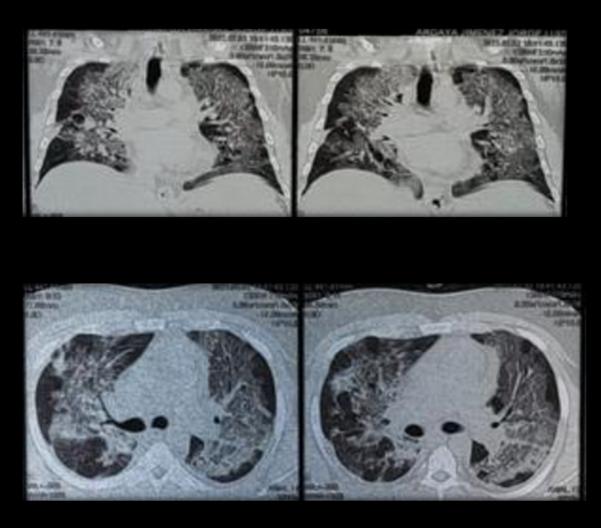

Mieloma múltiple con progresión extramedular subcutánea fulminante Multiple myeloma with fulminating extramedulary subcutaneous progression

Valeria Estefania Molina Cabrera, Ivanova Saavedra Tapia ......................................................................48-54